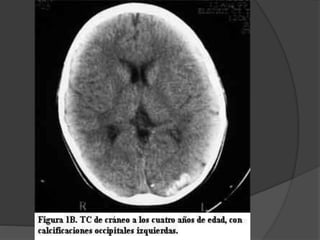

Enfermedad de Sturge-Weber Angiomatosis encefalotrigeminal  Etiopatogenia desconocida  Mas frecuente dentro de los sindromes neurocutaneos con predominio de anomalias vasculares.

La lesion fundamentales una malformacion vascular de tipo telangiectasico-venoso que afecta:  la coroides (angioma coroideo)  la cara (angioma facial)  el cerebro (angioma leptomeningeo) Puede ser del mismo lado, bilateral o presentarse inclompleto. Mancha en vino de oporto

Otras afecciones  Buftalmos Glaucoma  Epilepsia  Calcificaciones cerebrales  Retraso mental  Hemianopsia  Hemiparesia